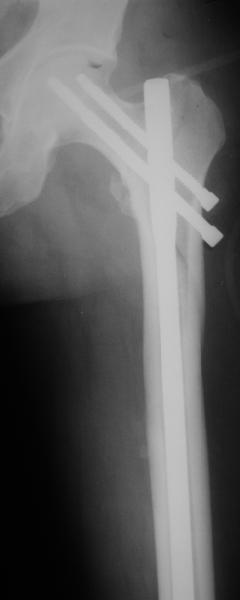

Как раз недавно у меня был примерный случай: больному 36 лет, поступил ночью, травма в результате мотоциклетной аварии, кроме чрезвертельного и спирального перелома левого бедра имеется переломы костей предплечья с этой же стороны. Скелетное вытяжение, а на следующий день больной про оперирован на ортопедическом столе с дистракцией. Чтобы не расколоть чрезвертельный перелом провели временную спицу ближе к переднему кортексу, из малого разреза костодержатель для репозиции, а фиксацию провели антиградным штифтом. Этапы операции на снимках.

Да, сейчас это и у нас самый напрашивающийся выбор. Сделали гвоздем ChM, картинки в приложении.